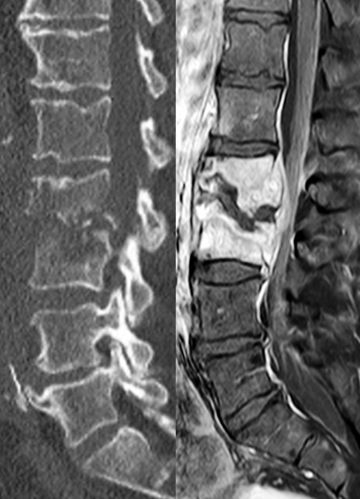

MRT und CT sind entscheidend für die präzise Diagnose einer Spondylodiszitis. Während das CT schnelle und detaillierte Informationen über die Knochenstruktur liefert und Zerstörungen oder Deformitäten aufzeigt, ermöglicht das MRT eine umfassende Beurteilung des entzündlichen Prozesses und des Weichteilgewebes. Beide Verfahren ergänzen sich ideal, um die genaue Lage und Ausdehnung der Entzündung zu bestimmen und eine gezielte, effektive Therapie zu ermöglichen.

Auf den Bildern ist eine Wirbelkörperentzündung der Lendenwirbelkörper 2 und 3 zu sehen. Beim linken Bild zeigt das CT eine Zerstörung des Knochens und ein beginnendes „Ineinandersinken“ der Wirbelkörper. Das MRT zeigt auf der rechten Seite eine deutliche Signaländerung der Wirbelkörper (heller) als Ausdruck eines entzündlichen Prozesses. Zusätzlich wird ein Abszess im Rückenmarkskanal sichtbar, welcher den Rückenmarkskanal einengt und zu Ausfallerscheinungen führt (beginnende Querschnittsymptomatik).